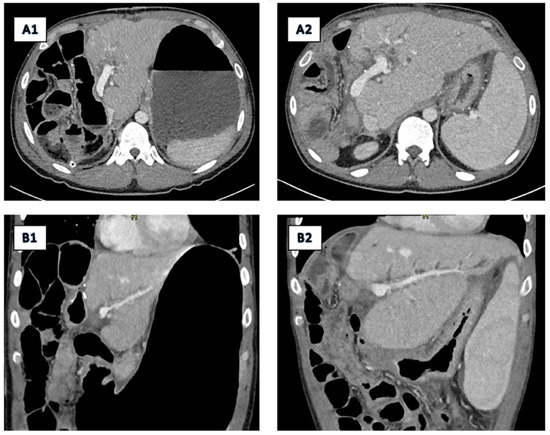

2.2. Imaging